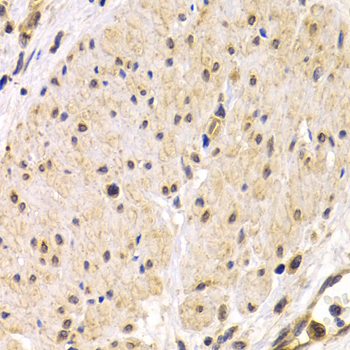

• A1979: image 2

Immunohistochemistry of paraffin-embedded human stomach cancer using TMPRSS2 antibody at dilution of 1:200 (400x lens).